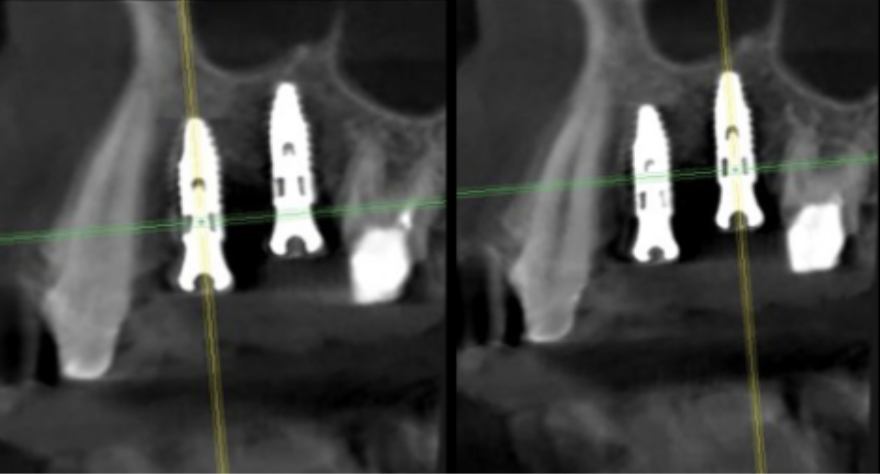

インプラント埋入前のCTによる確認